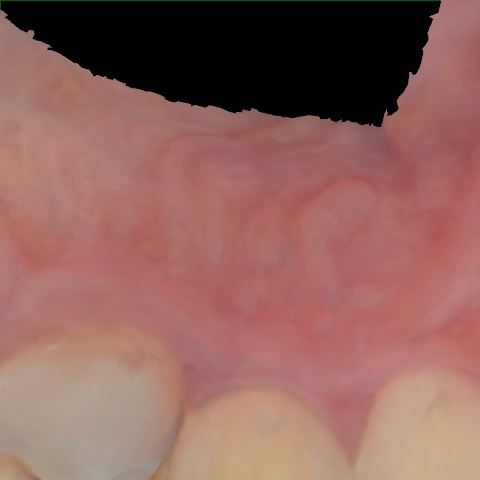

NHD39990

Annotated as "Good"